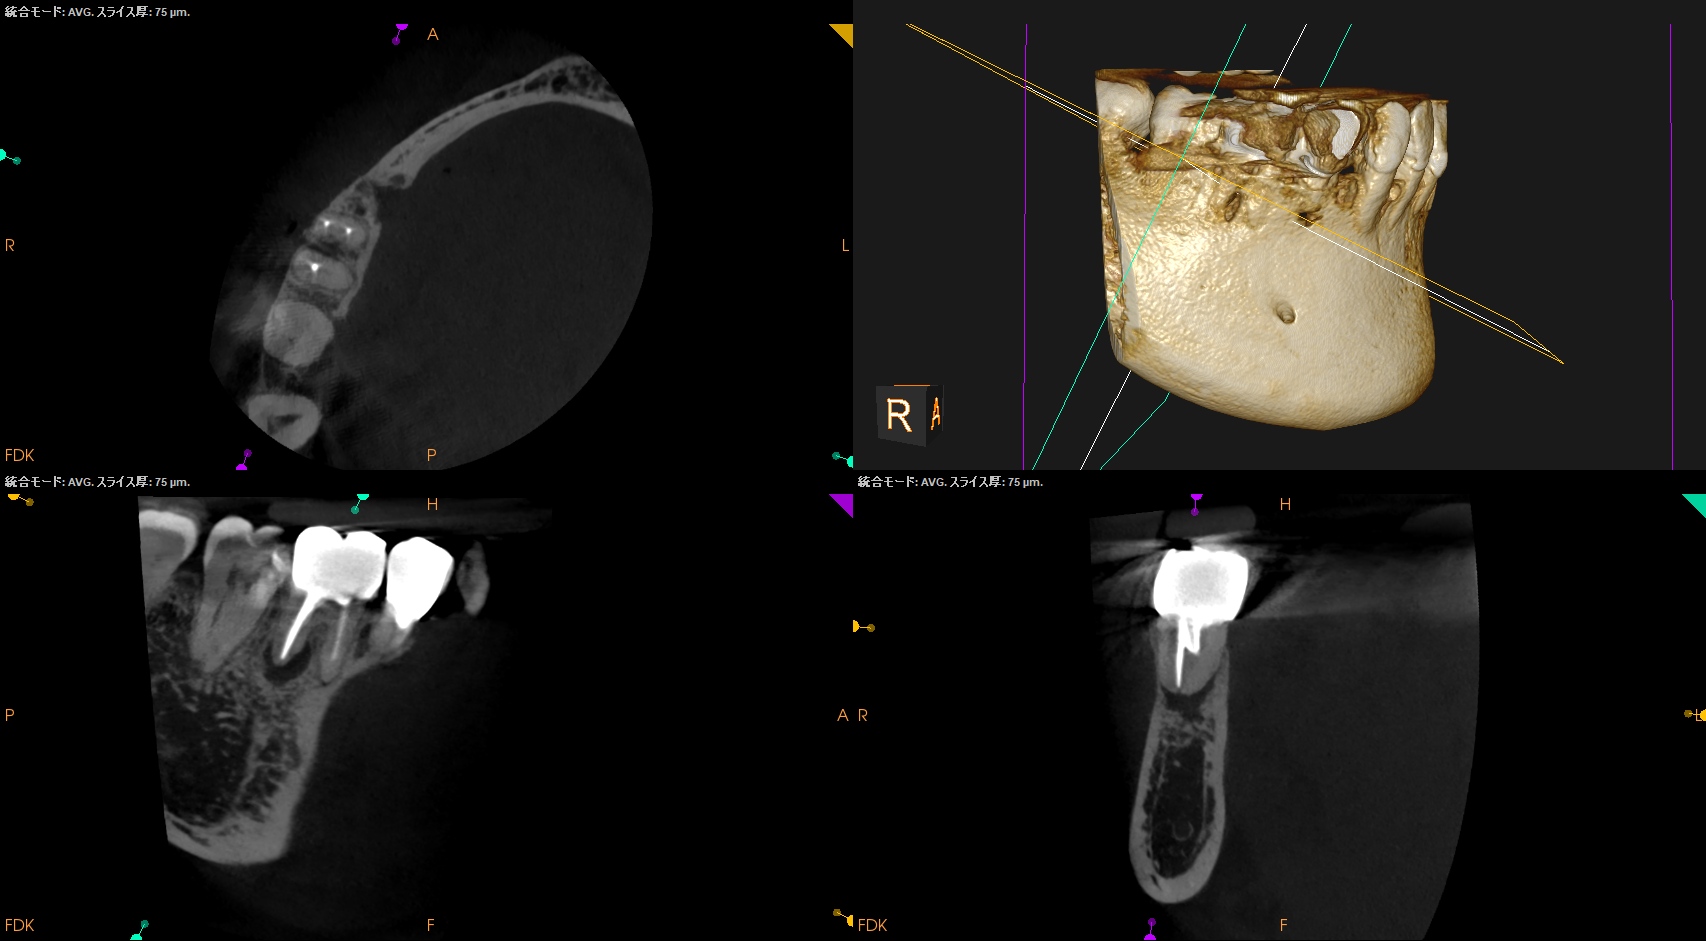

MB

ML

D

以下のような術式で行われるべきでああろう。

私にはD根が歯槽骨から透けて見える。

PA, CBCTを撮影した。